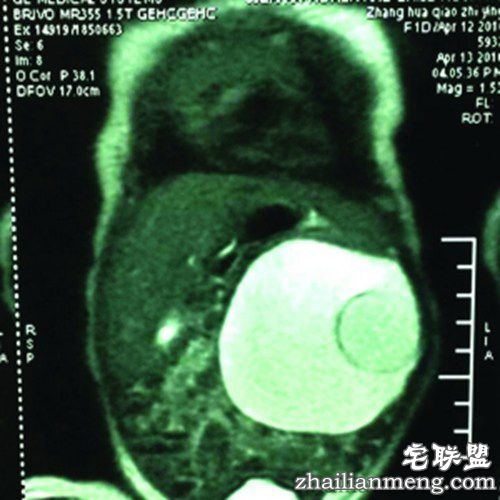

原来,李先生的妻子怀孕两个月时,发现胎儿腹中有肿块,后被确诊为畸胎瘤。医生在征求李先生夫妇同意后,建议他们采取随诊、随访的措施进行诊疗。

今年4月13日,女婴苗苗通过剖宫产顺利降生。降生第二天,苗苗便在淮安市妇幼保健院接受术前准备。4月19日,在经历数小时的手术后,医生顺利从苗苗腹中取出了已经长了双脚和头颅的胎儿。

该院主任医师王寿青介绍,苗苗腹中的胚胎属于“寄生胎”,如果不及时手术,会发生感染、分散性恶化等后果,可能危及生命。

这样的“胎中胎”是如何形成的?医生说,苗苗妈妈怀的是双胞胎,孪生胚胎在发育时,一个胚胎被包入另外一个胚胎之中。当包入的那个胚胎发育成型,也就是苗苗被分娩后,被包入的胚胎存在她的腹腔中,同时随着她一起生长,且畸形发展。